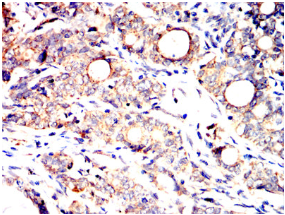

SLC2A14 Mouse Monoclonal antibody[8E10E]

Immunogen:    Purified recombinant fragment of human SLC2A14 (AA: extra mix) expressed in E. Coli.

IHC    1/200 - 1/1000